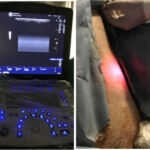

Θεραπεία Κιρσών με laser

Η θεραπεία κιρσών με laser είναι μια ελάχιστα επεμβατική μέθοδος κατά την οποία εφαρμόζεται ενδοφλέβια θερμική ενέργεια για να κλείσει η πάσχουσα φλέβα και να αποκατασταθεί η φυσιολογική φλεβική κυκλοφορία.